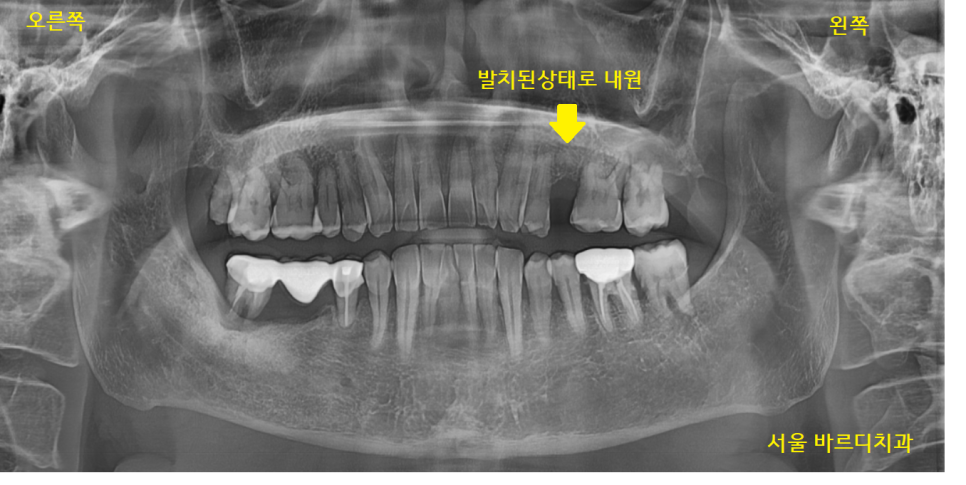

22.12.19

환자분이 처음 내원하셨을 때 사진입니다.

왼쪽 위 어금니 1개가 없는 상태로

방문해 주셨습니다.